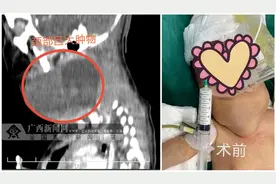

来源:杭州日报 @各位家长,孩子脖子上如果有鼓包 千万留心!尤其要注意有没有变大...... 前段时间,11岁的欢欢(化名)总是吵着脖子不舒服,吃饭时感觉脖子会卡住,妈妈用手一摸,在脖子右侧摸到一个鼓包。欢欢妈妈以为是孩子这几天上火了,过几天清淡饮食的生活可能就没事了。